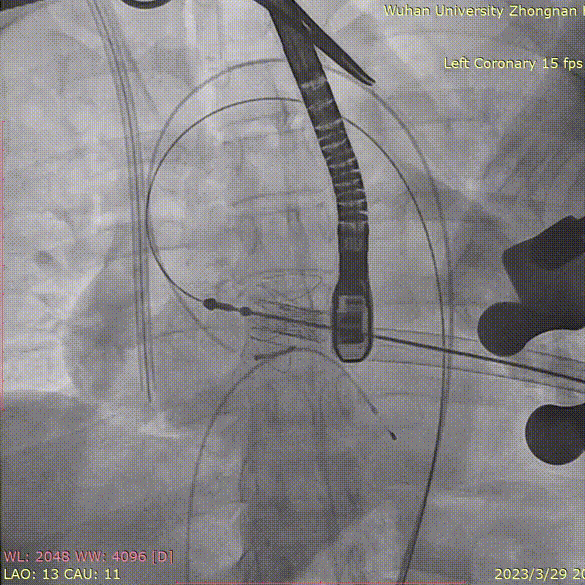

释放瓣膜,复查根部造影,未见明显反流,瓣膜形态和位置满意,双侧冠脉未见遮挡征象:

退出介入器:

血管减影造影,瓣膜形态正常、未见瓣周漏: